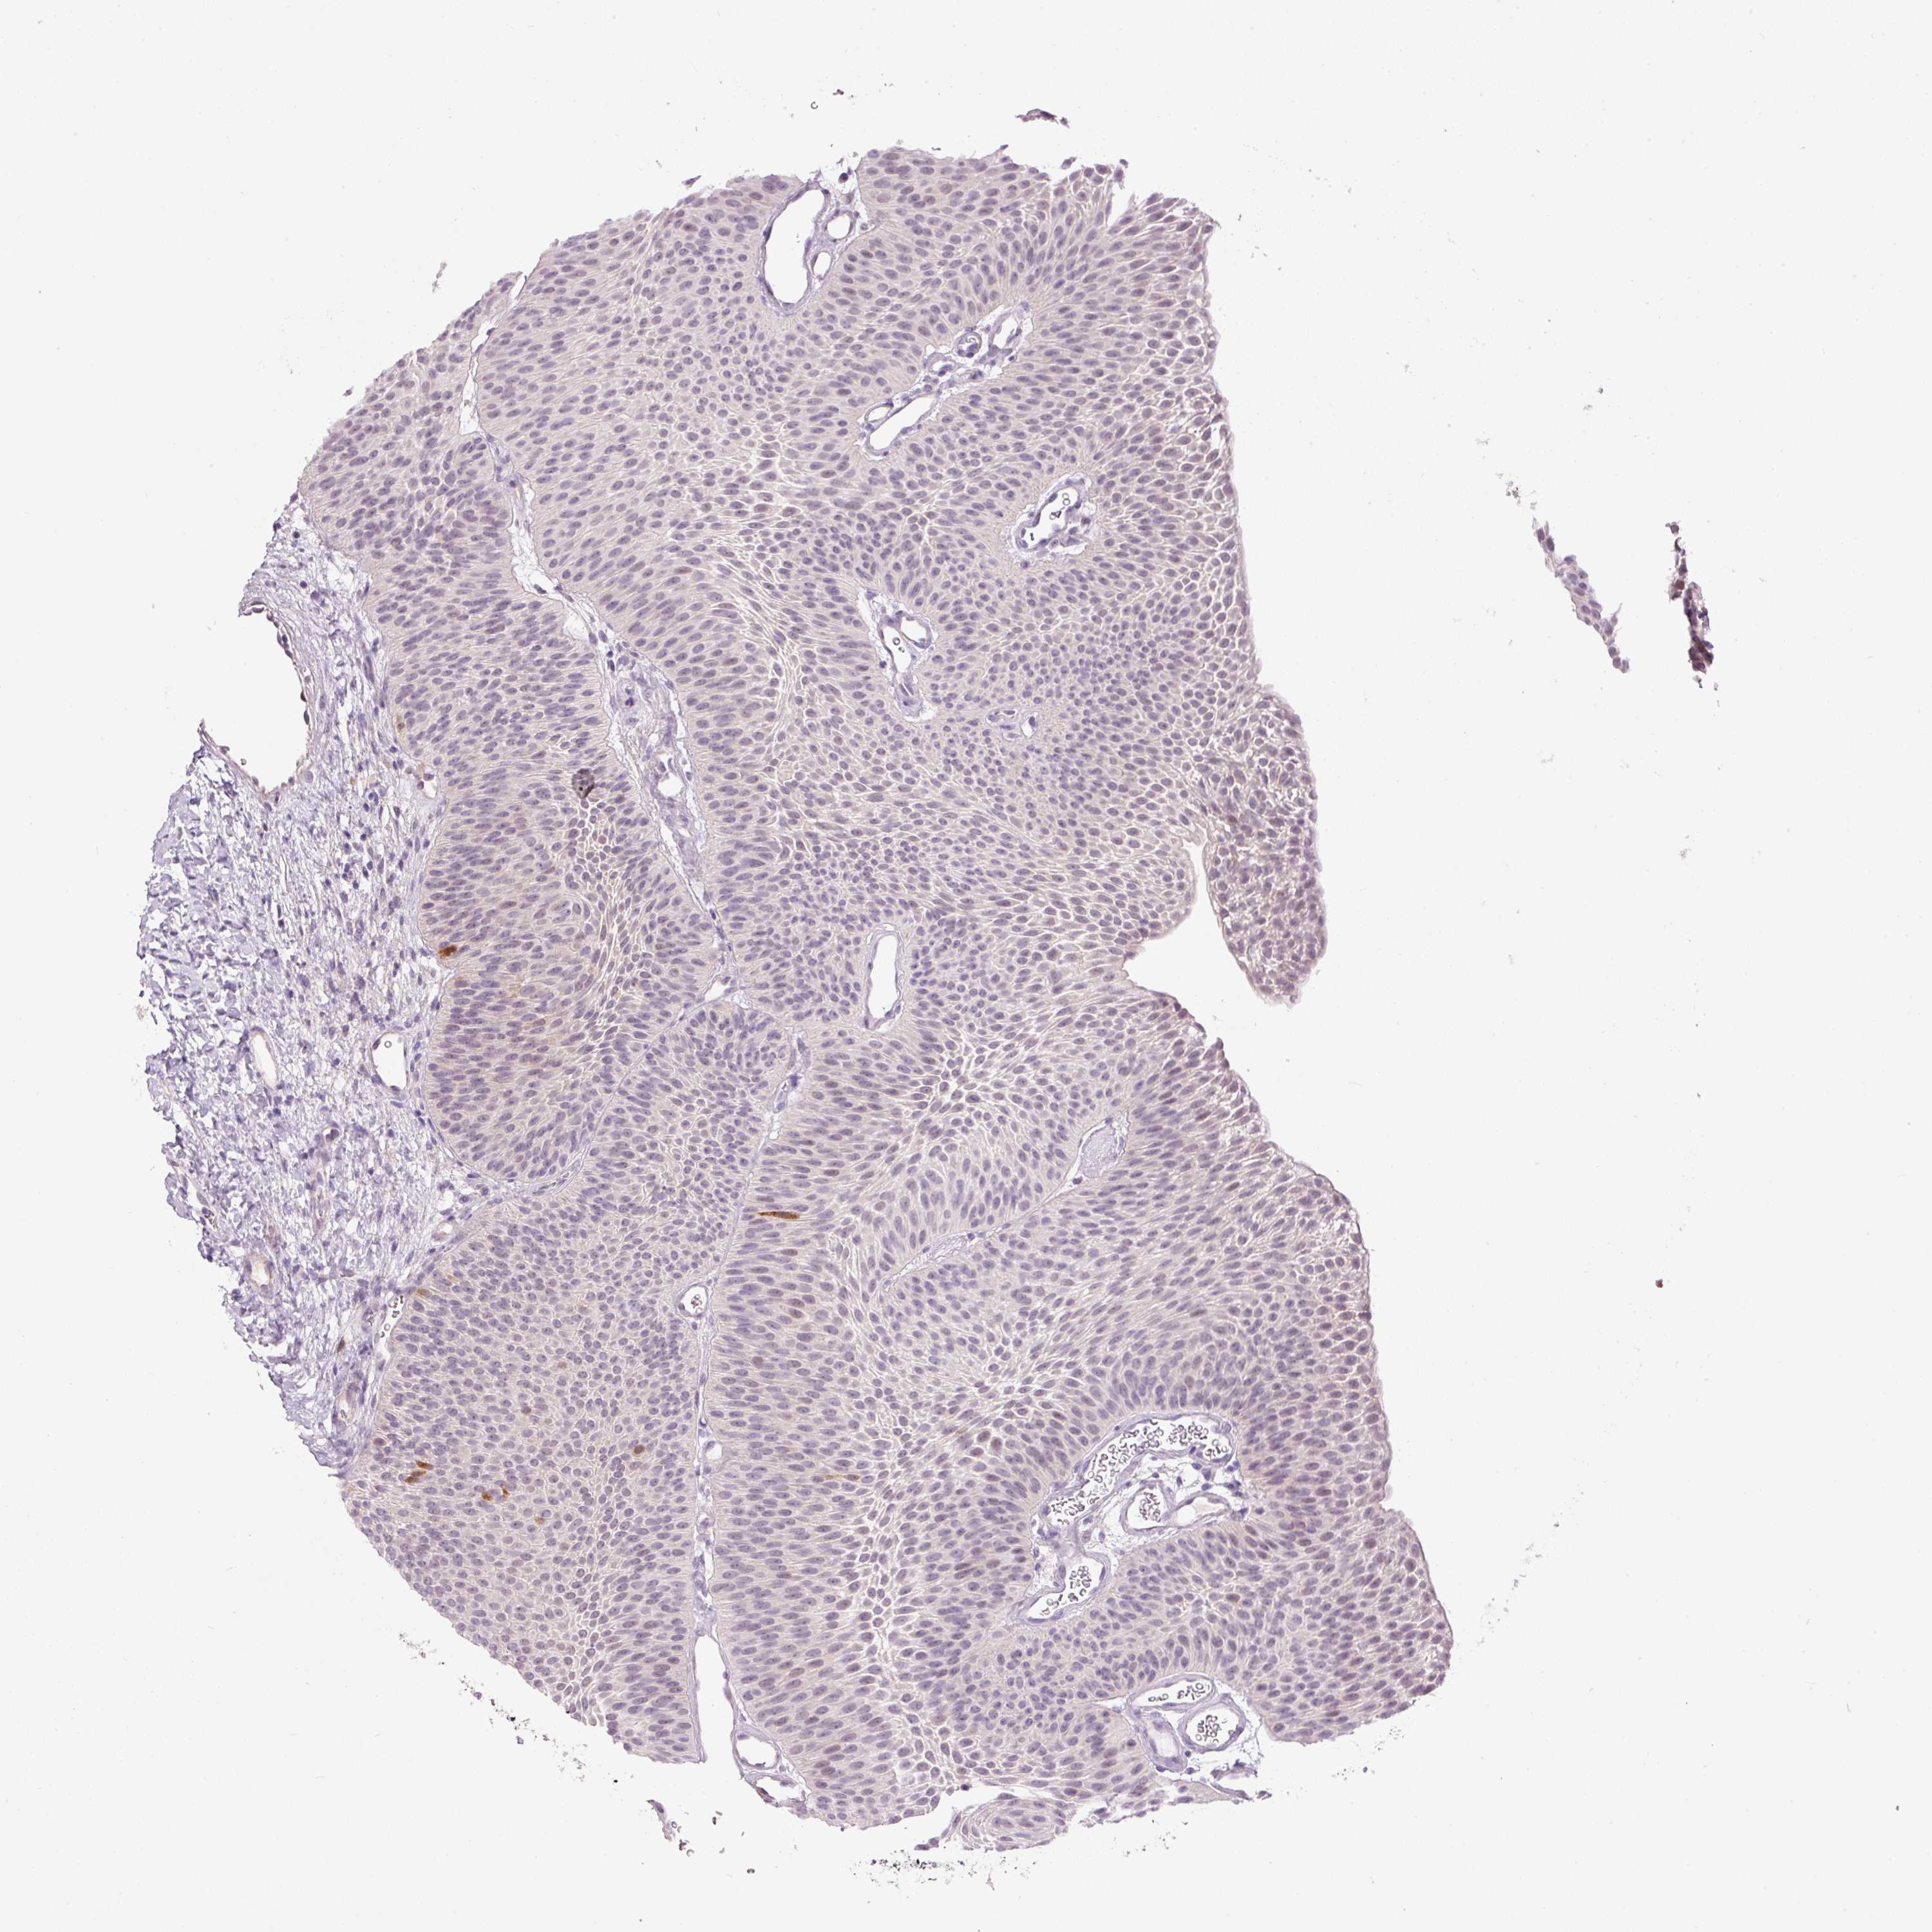

UROTHELIAL CANCER - Protein expressioni

A mouse-over function shows sample information and annotation data. Click on an image to view it in a full screen mode. Samples can be filtered based on level of antibody staining by selecting one or several of the following categories: high, medium, low and not detected. The assay and annotation is described here.

Note that samples used for immunohistochemistry by the Human Protein Atlas do not correspond to samples in the TCGA dataset.

Antibody stainingi

Antibody staining in the annotated cell types in the current human tissue is reported as not detected, low, medium, or high, based on conventional immunohistochemistry profiling in selected tissues. This score is based on the combination of the staining intensity and fraction of stained cells.

Each image is clickable and will lead to virtual microscopy that enables deeper exploration of all samples and also displays staining intensity scores, fraction scores and subcellular localization as well as patient and tissue information for each sample.

Antibody HPA041270

Antibody CAB015460

Staining

High

Medium

Low

Not detected

Intensity

Strong

Moderate

Weak

Negative

Quantity

>75%

75%-25%

<25%

None

Location

Nuclear

Cytoplasmic/membranous

Cytoplasmic/membranous,nuclear

Urothelial carcinoma, Low grade